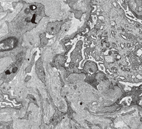

3例患儿(例2、例6、例7)进行了肾脏穿刺活检,光镜检查均可见肾小球系膜细胞和基质不同程度弥散或节段增生,毛细血管襻内皮细胞增生及肿胀;小动脉管壁增厚,部分小动脉壁葱皮样增生,可见毛细血管腔内淤血伴微血栓形成。2例患儿免疫荧光染色可见系膜区轻度IgG、IgM和C3沉积,1例免疫荧光染色均为阴性。电镜检查可见毛细血管内皮细胞肿胀,基底膜内疏松层增厚,见图1。